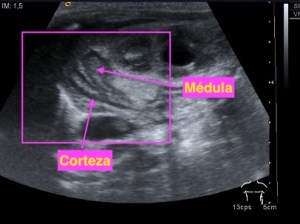

- Vesícula biliar: Visualizada como una estructura en forma de pera, que puede variar en tamaño según la cantidad de bilis que contenga. Su pared aparece como una línea hiperecogénica y suele tener un grosor menor a 3 mm.

- Lumen: Es la cavidad interna de la vesícula biliar donde se almacena la bilis. Se visualiza como una zona anecoica (sin ecos) rodeada por la pared hiperecogénica.